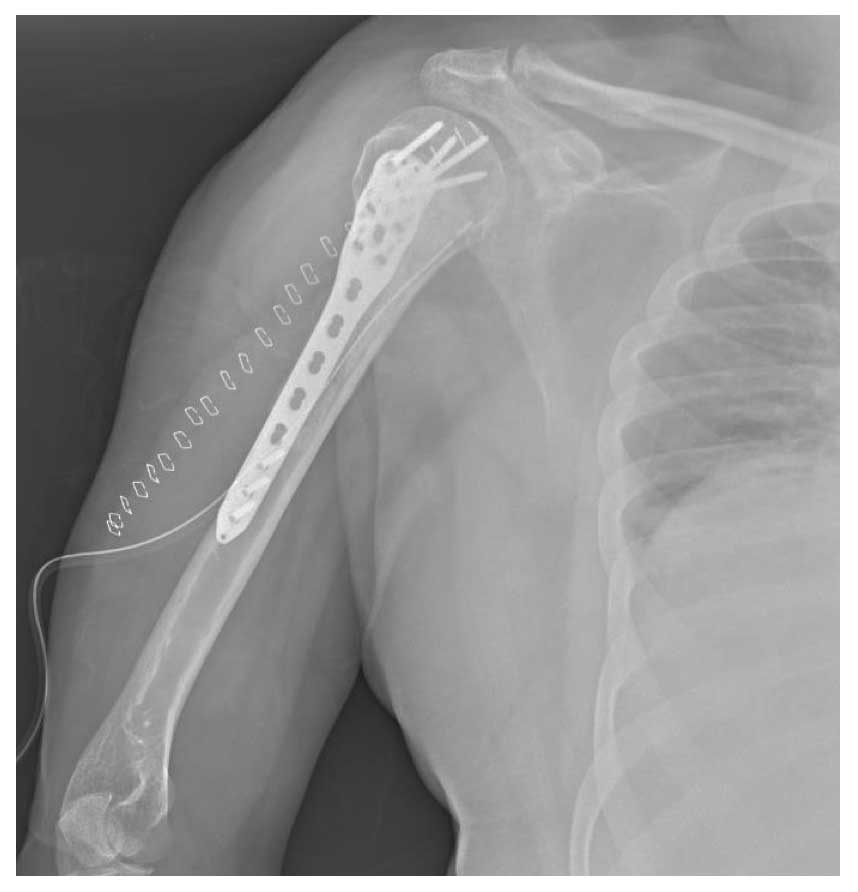

Ameliyat Sonrası: Tümör temizlendikten sonra oluşan boşluğun kemik çimentosu ile doldurulması ve anatomik plak ile güçlendirilmesi görülmekte.